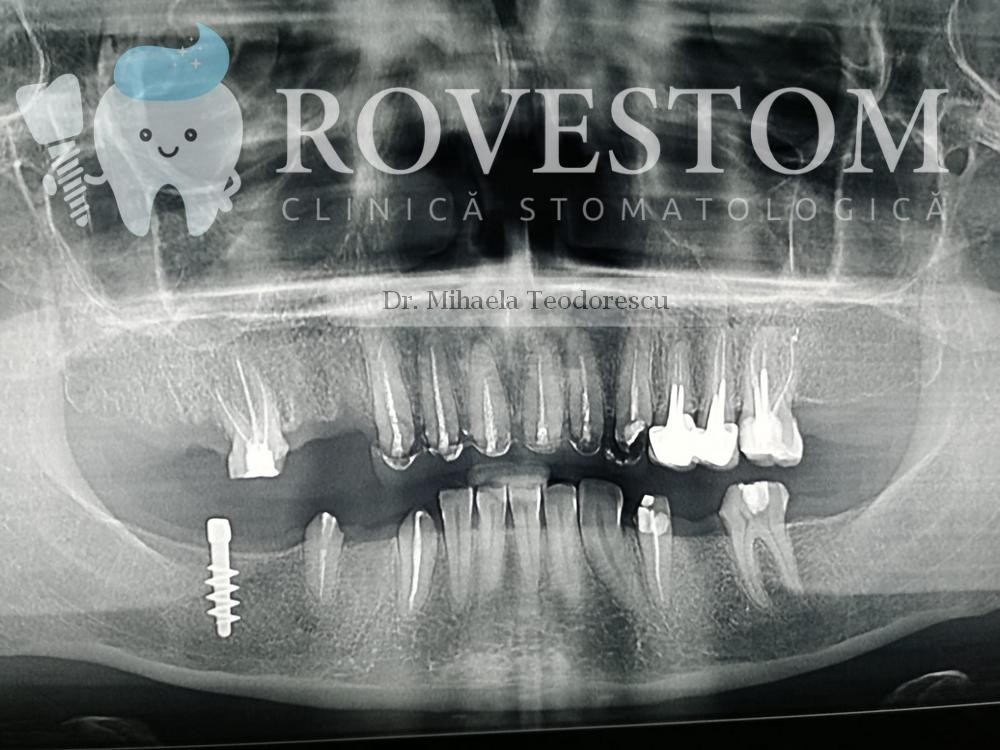

Implantologie